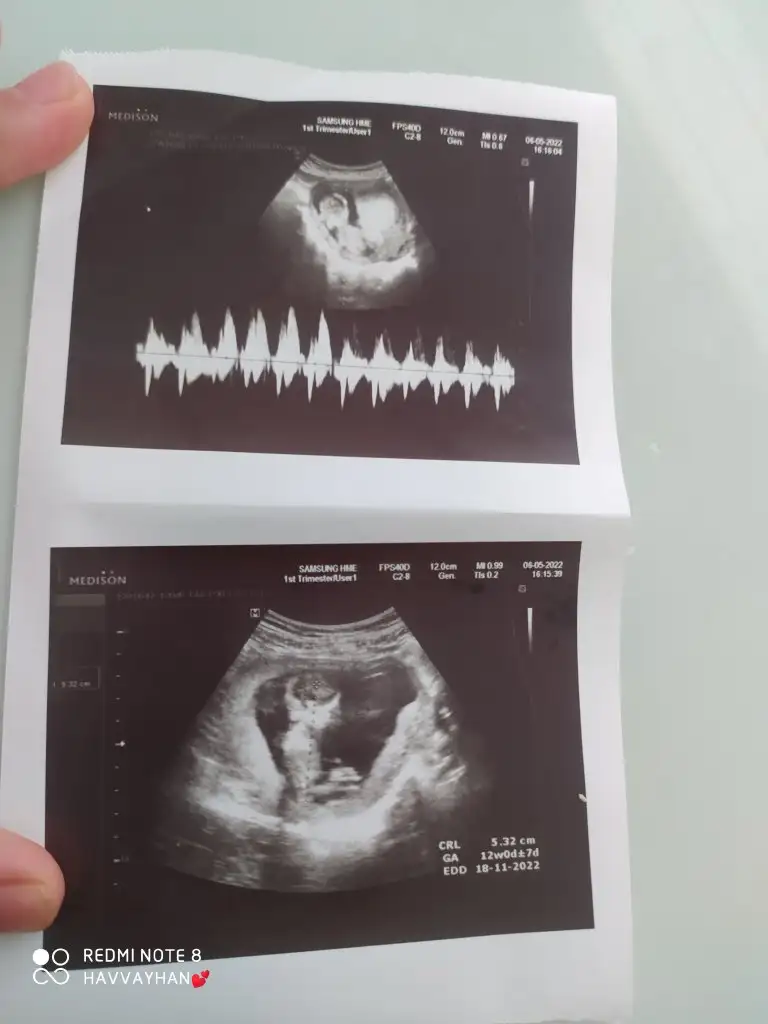

Merhabalarr, bende çook merak ediyorum ilk fotoğrafta 9+5 , ikinci de 12+1 bana da bakar mısınız rica etsemKız ve erkek görüntülerine çok bakmıştım.o yüzden tahmin edebiliyorum

Erkek yüksek bir ihtimalle canım Allah sağlıkla kucağına versin İnslalhMerhabalarr, bende çook merak ediyorum ilk fotoğrafta 9+5 , ikinci de 12+1 bana da bakar mısınız rica etsem![]()